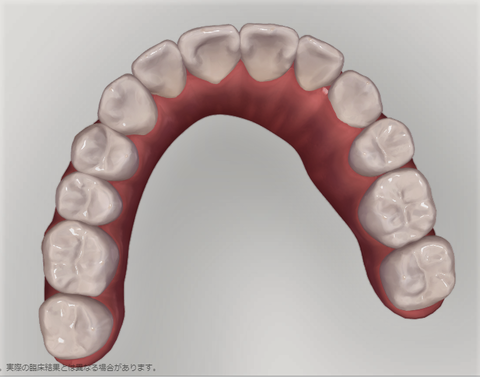

下の歯の比較

噛み合わせの比較。